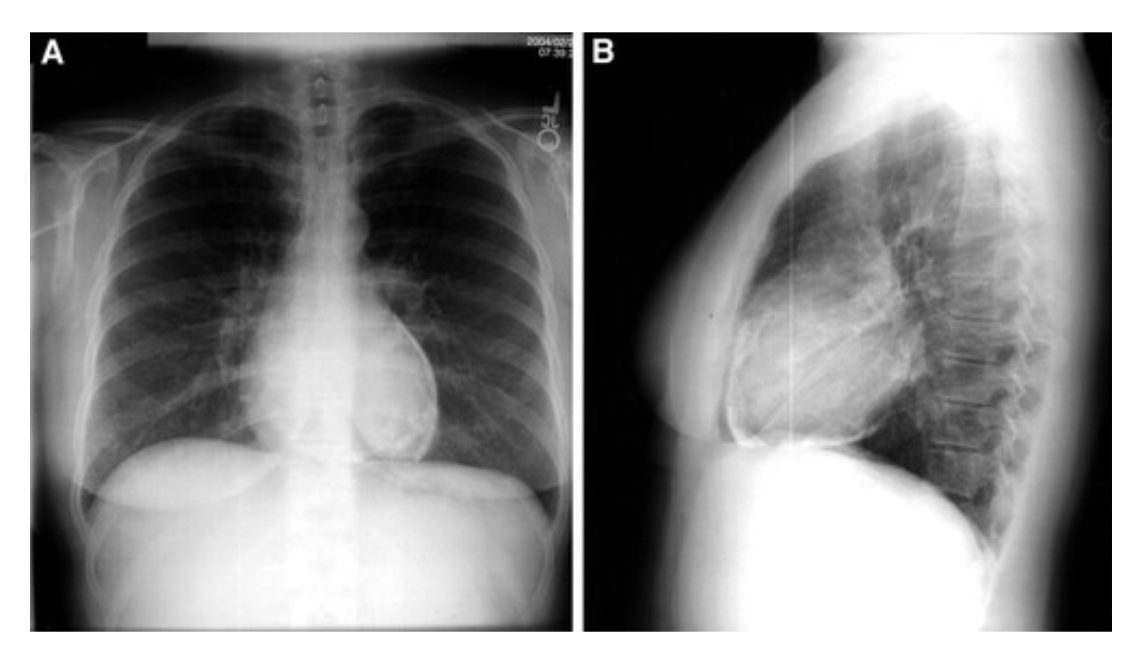

CXR findings in pericarditis.

Possible cardiomegaly if pericardial effusion.

CXR findings in constrictive pericarditis.

Small heart +/- pericardial calcifications.